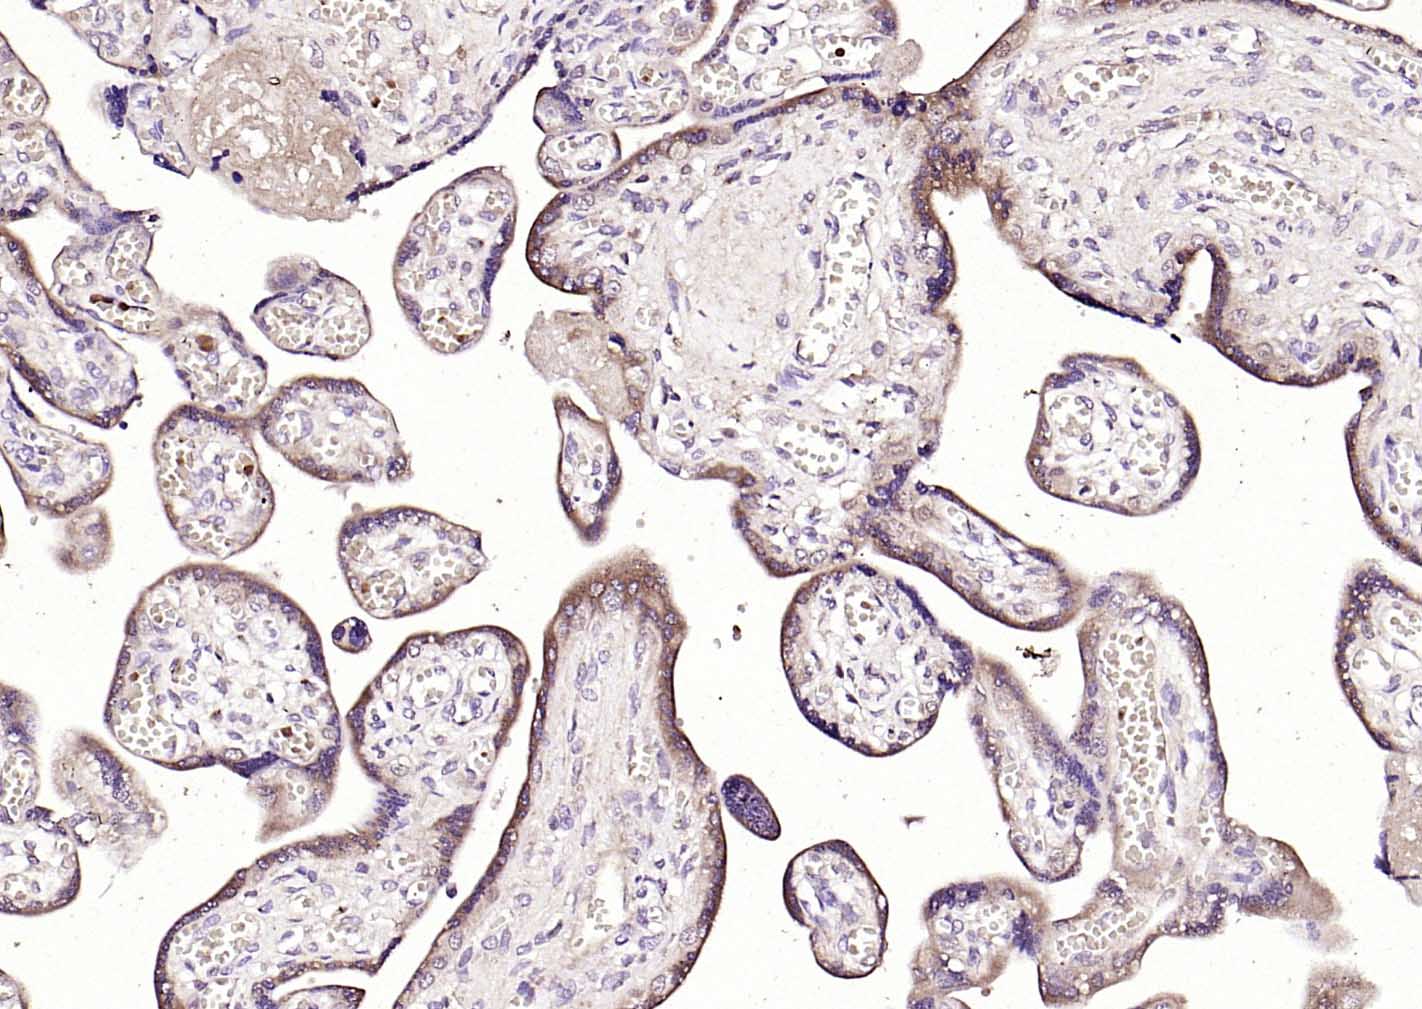

| IHC-P | Human, Mouse, Rat | Dog, Horse | 1:100-500 |